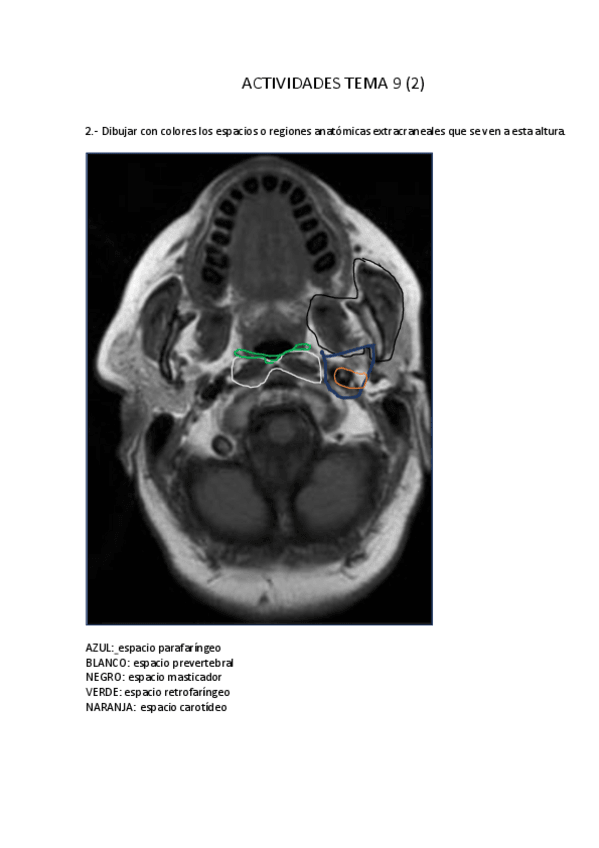

Apuntes - Tema-9-Cavidad-craneal.pdf

Apuntes - Tema-9.pdf